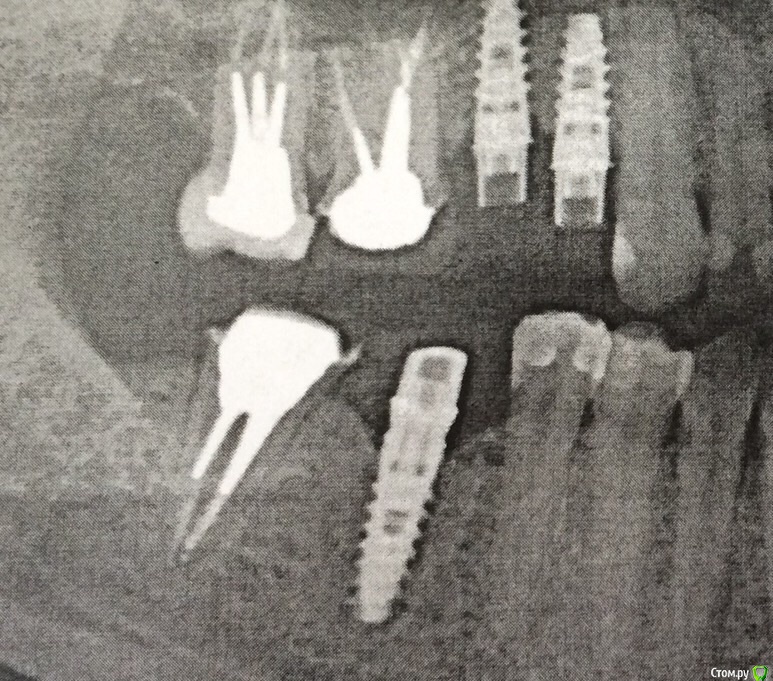

Nadiakroha Опубликовано 12 февраля, 2015 Поделиться Опубликовано 12 февраля, 2015 Здравствуйте! Недавно установили ВКВ из циркония. Мой врач обещал, что cad-cam вкладка идеально точная, но на снимке я вижу, что внутри корня вкладка не идеально прилегает, и как- будто там пустота или какой- то материал.. Подскажите, это нормально? Какие могут быть последствия в дальнейшем? В чем причина неточности, слепки или техник? Спасибо! Ссылка на комментарий

Evikrol Опубликовано 13 февраля, 2015 Поделиться Опубликовано 13 февраля, 2015 (изменено) Пустот нигде нет. Где вы видите пустое место? Изменено 13 февраля, 2015 пользователем Evikrol Ссылка на комментарий

Nadiakroha Опубликовано 14 февраля, 2015 Автор Поделиться Опубликовано 14 февраля, 2015 Вижу на верхней семерке, как мне кажется.. Просто доктор говорил, что Cadcam идеально точно, вот и возникли сомнения.. Ну нет, так нет, я только рада!!) Ссылка на комментарий